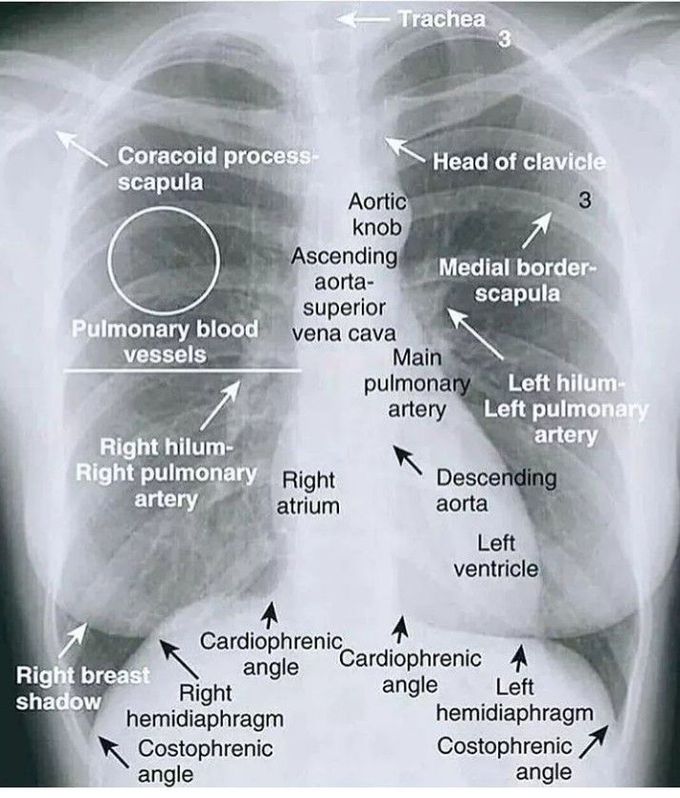

Normal Chest Xray Labeled Chest X Ray Signs In fact every radiologst should be an expert in. This poster is published under an open license. This presentation reviews 30 classic radiological signs of chest. Please read the disclaimer for further details. To provide knowledge about the features related to each sign and. Chest X Ray Signs.

Normal, Labelled, Chest xray Undergraduate Diagnostic Imaging Fundamentals Chest X Ray Signs To provide knowledge about the features related to each sign and. Please read the disclaimer for further details. This poster is published under an open license. In fact every radiologst should be an expert in. This presentation reviews 30 classic radiological signs of chest. Chest X Ray Signs.

Normal Chest X Ray Labeled Chest X Ray Signs This poster is published under an open license. In fact every radiologst should be an expert in. This presentation reviews 30 classic radiological signs of chest. To provide knowledge about the features related to each sign and. Please read the disclaimer for further details. Chest X Ray Signs.